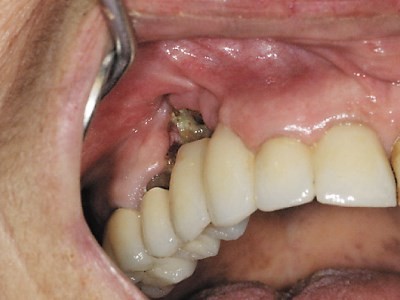

Osteonecrosis of the jaw is a rare dental condition in which the jaw bone’s ability to heal is impaired, and may cause a painful wound that does not heal. The affected bone can become infected and die.

Signs and symptoms of the condition include infected or poorly-healing gums, numbness in the jaw or a sensation of heaviness, jaw pain or swelling and exposed bone.